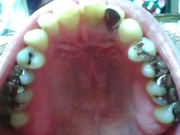

それ以外にも笑うと写真のように奥まで見えます。

写真を拝見致しましたが、これだけでは保険適用が可能かどうかを判断するのは困難です。